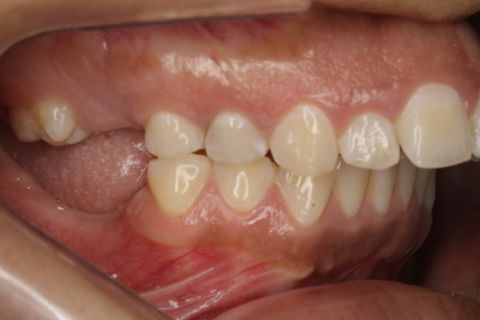

Foto Inicial.